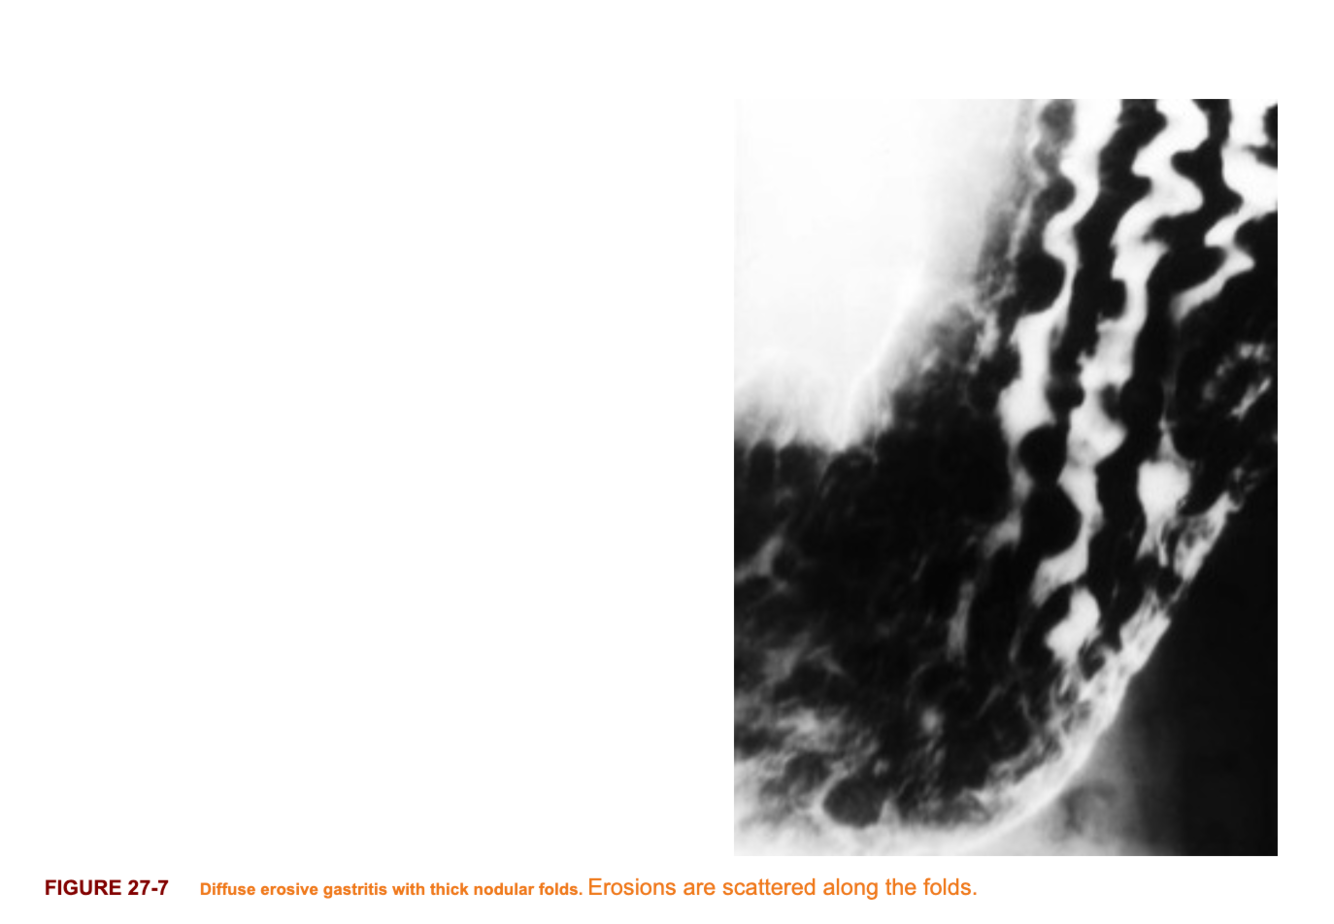

Imaging features of Gastritis

- Multiple tiny, apthoid like erosions throught the antrum and boy of the stomach

- Occurs on rugal folds

- Prominent area gastricae